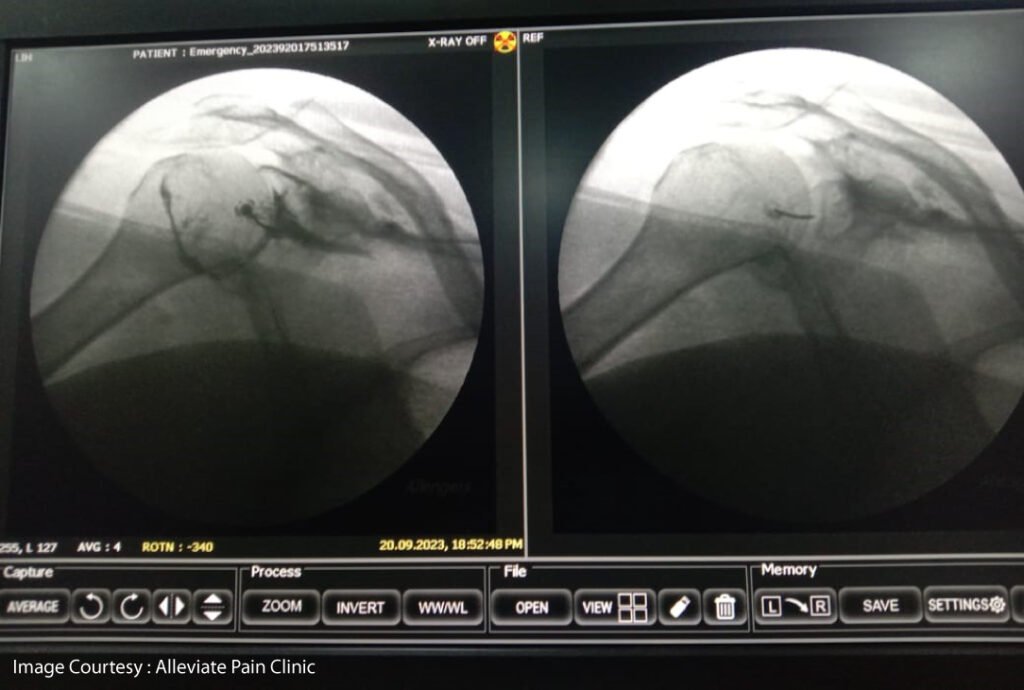

- Hydrodilatation : This procedure involves injecting sterile water into the joint capsule to stretch it and improve range of motion.

AT ALLEVIATE, we have seen more than 90% success rate with frozen shoulder patients treated with our combined approach involving hydrodilatation, suprascapular nerve block and manipulation followed by 2-3 weeks of physical therapy.

HYDRODILTATION UNDER FLUOROSCOPIC GUIDANCE

Suprascapular Nerve Block using Fluoroscopy